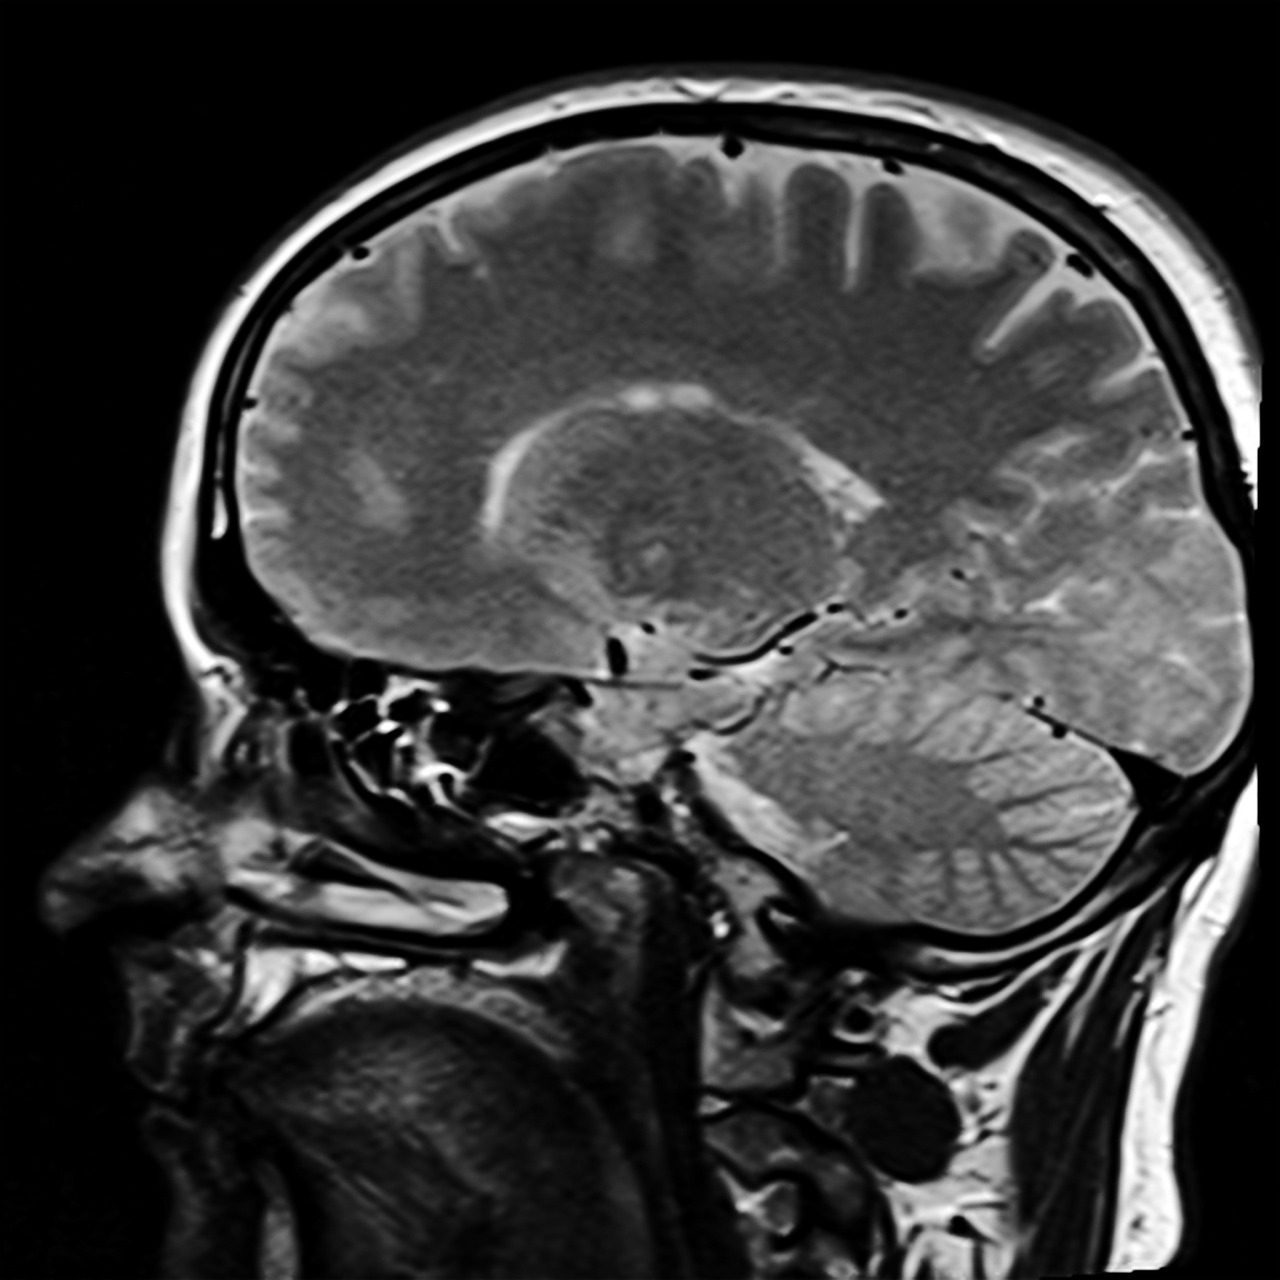

Former Israeli Prime Minister’s Significant Brain Activity – How Do We Know?

Israeli scientists and UCLA’s Dr. Martin Monti recently found that former Prime Minister Ariel Sharon demonstrates significant brain activity. Seven years ago Sharon suffered two strokes. The second stroke caused him to lose most of his consciousness. Sharon is in a minimally conscious state, a little more aware than a coma or a persistent vegetative…